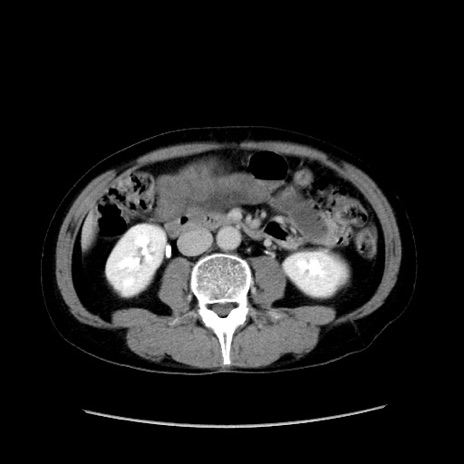

症例37(横断像)

【症例】40歳代 男性

【主訴】腹痛

【現病歴】4時間ほど前に電車に乗車中に臍部上より腹痛出現。徐々に増悪し起立困難となり、救急外来受診。生ものは数日食べていない。今朝お雑煮を食べた。

【身体所見】BT 36.8℃、BP 117/84mmHg、HR 91/min、SpO2 97%、苦悶様、腹部:臍上部広範囲圧痛あり、反跳痛±

【データ】WBC 8100、CRP 0.03